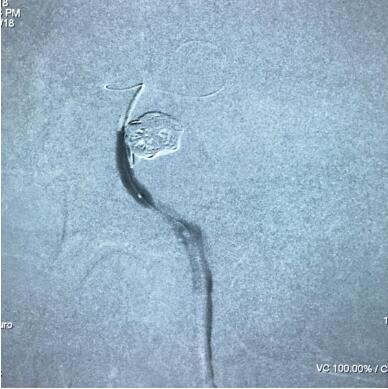

造影便发现是右侧颈内动脉海绵窦段的夹层动脉瘤了!动脉瘤不规则,结合磁共振检查我们断定动脉瘤是伴有血栓形成的,造影显示的只是它的"芯"。这种动脉瘤会经常发生形态变化,还会不断象"洋葱皮样"生长,可以形成压迫症状(如头疼、面部麻木、眼球运动困难、眼睑下垂等),也可以造成脑梗死。这种情况必须积极治疗。

我们先在瘤内放置一根微导管,以备支架不能完全封闭时用弹簧圈疏松填塞来补救,这是打开支架的情况。结果怎样呢?